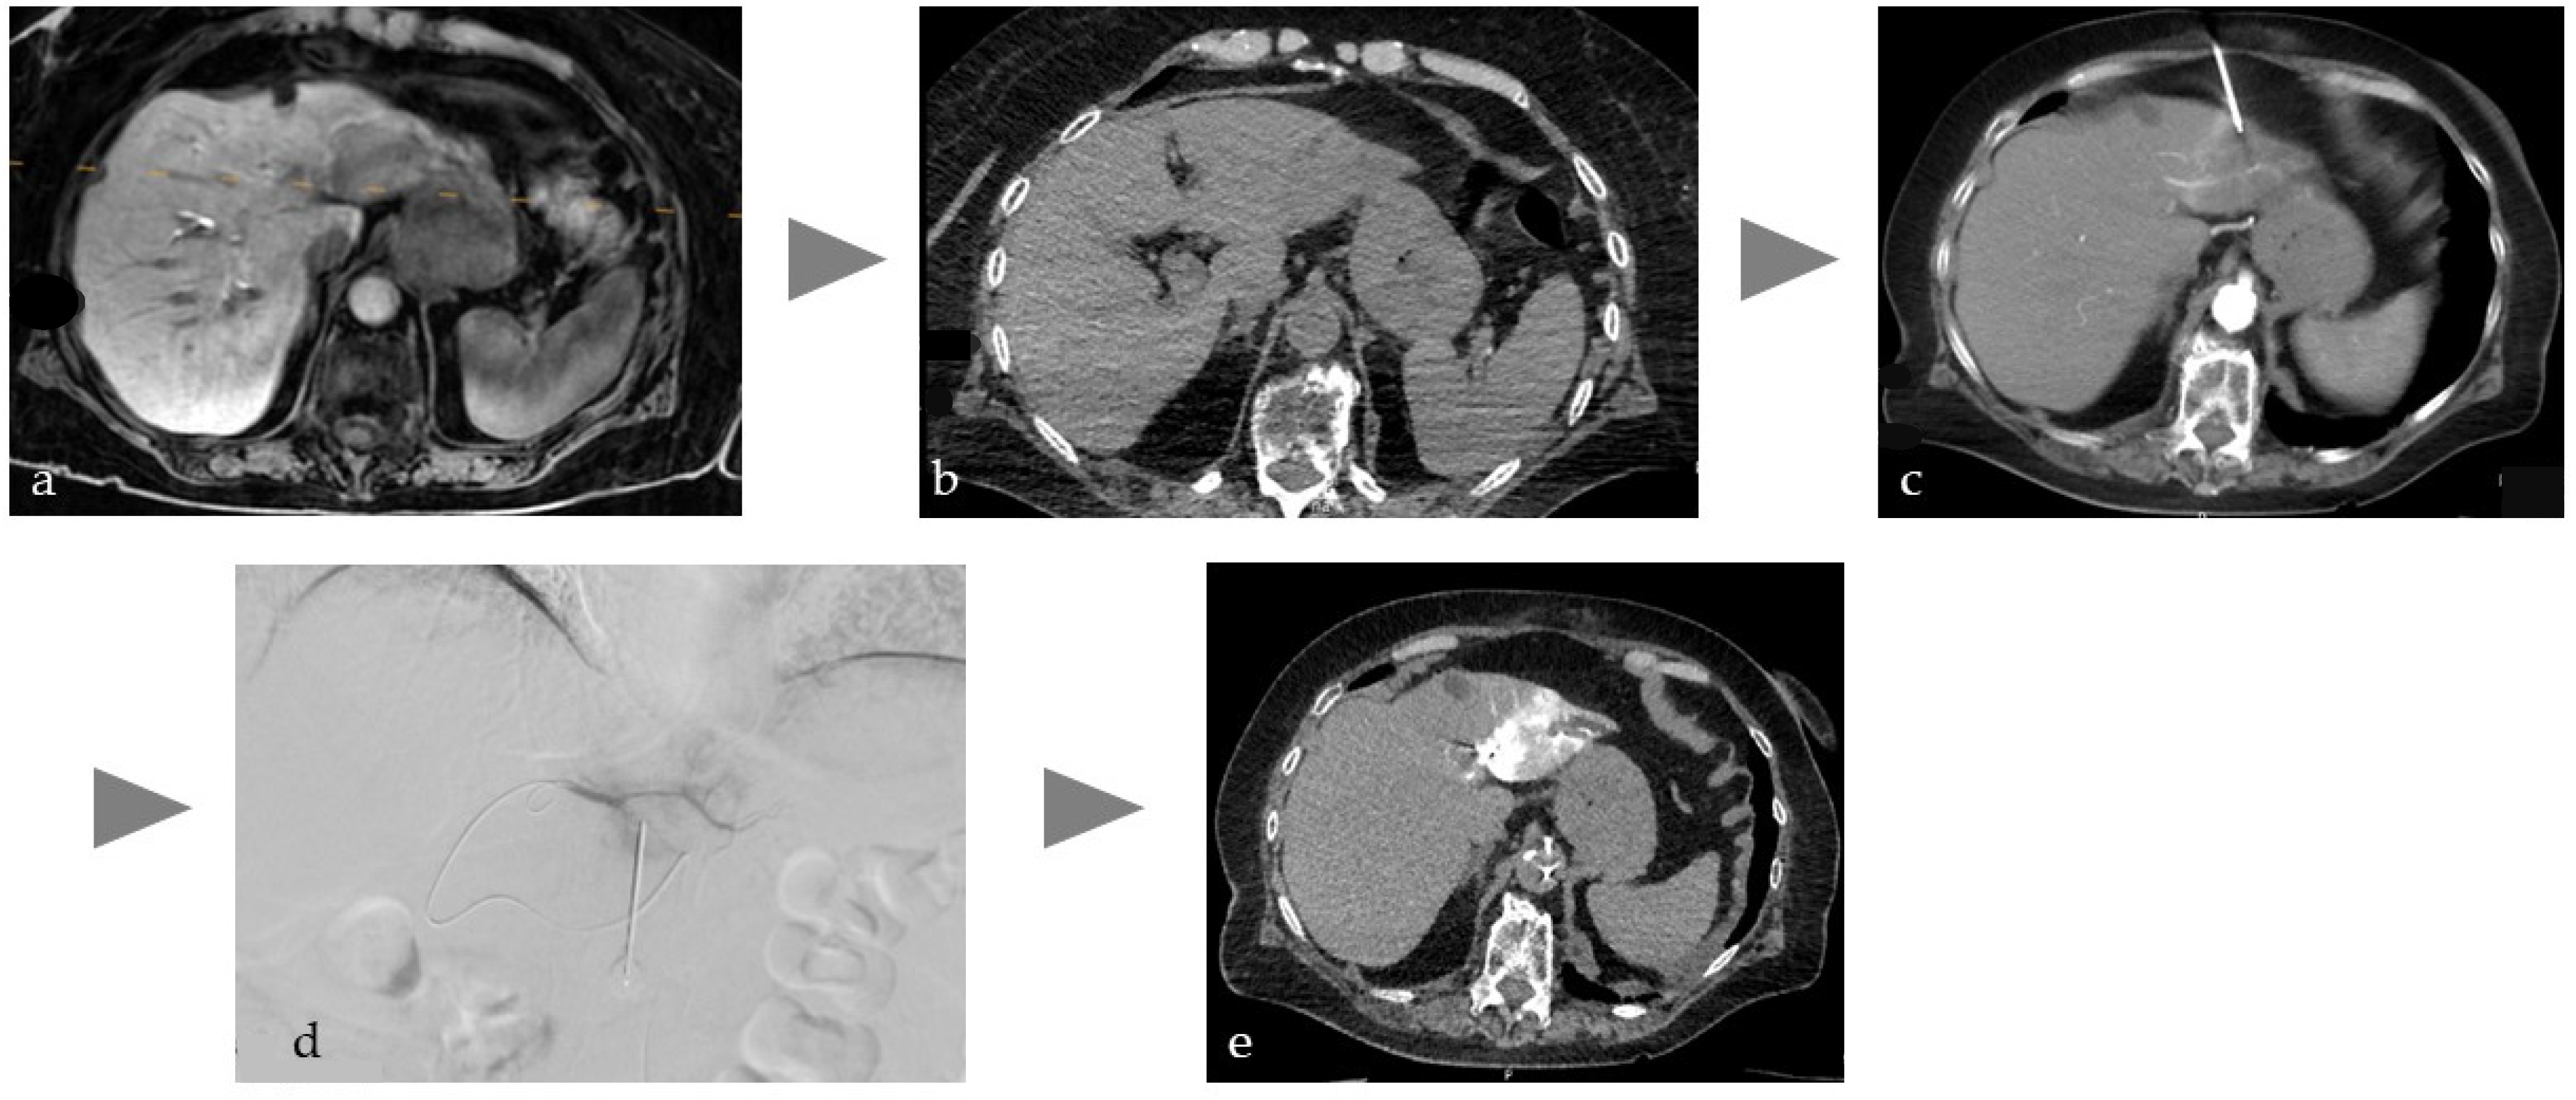

In the context of tissue devascularization procedures, the concept of super-selective treatment assumes particular significance in the scope of PAE for the treatment of symptomatic BPH, given the notable proximity of the structures at risk. The success of the treatment depends on the identification of the tiny, highly variable feeding vessels and their collaterals [59,60]. This leads to relatively complex procedures with potentially increased radiation dose to the patient and medical staff. Due to the lack of adequate imaging in the early days of PAE, complications due to ischemia in the rectum, bladder, and penis sometimes occurred, although rarely [60]. Consequently, the current consensus on the imaging workflow involves performing a preprocedural CT or MR angiography followed by an intraprocedural selective CBCT scan of each internal iliac artery to identify the relevant feeding prostate arteries. In the second step, the end-stream route intended for embolization must be verified by an additional distal super-selective CBCT to avoid complications associated with non-targeted embolization [61]. As preoperative cross-sectional imaging is not part of the routine BPH clinical workup, a group of experts recently published an innovative viewpoint to perform PAE without preprocedural CT or MRI but in a single session with high-resolution intraprocedural imaging. The authors of this study hypothesize that an Angio-CT suite will allow for a dedicated one-stop workflow with high soft tissue contrast planning images without motion artifacts, like conventional ceCT, and excellent super-selective imaging for precise targeting [62]. This workflow is illustrated in Figure 2.

Figure 2. Typical workflow for prostatic artery embolization in benign prostatic hyperplasia (BPH): (a) optional pre-interventional MRI to visualize the hyperplasia and exclude tumors, (b) intra-arterial CT angiography with 100 mL volume, with 1:10 dilution corresponding to approx. 10 mL CM at the beginning of the intervention to identify the prostate arteries, (c) software-based marking of the prostate artery and overlay on fluoroscopy, (d,e) After super-selective probing of the right and left prostate artery, DSA and CT were performed to ensure selective targeting of prostate tissue.